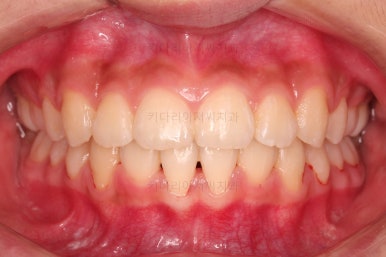

1. 초진 시 입안의 모습 평가

부산치아교정치과 키다리아저씨치과에 처음 내원했을 당시의 입 안의 모습입니다.

전반적으로 윗니가 나와있는 양상이고요.

앞니는 뻐드러져 있네요.

아래 앞니는 위로 솟구쳐 올라서 윗니 뒤쪽을 강하게 치고 있는 과개교합 양상이었고요.

위아래 앞니쪽이 삐뚤어져 있는 상태였습니다.